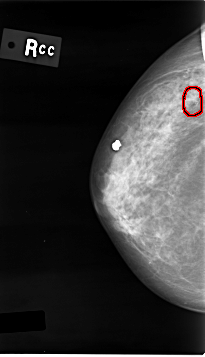

C_0012_1.RIGHT_CC

RIGHT_CC LINES 4640 PIXELS_PER_LINE 2656 BITS_PER_PIXEL 12 RESOLUTION 50 OVERLAY

FILE: C_0012_1.RIGHT_CC.OVERLAY

TOTAL_ABNORMALITIES 1

ABNORMALITY 1

LESION_TYPE CALCIFICATION TYPE PLEOMORPHIC DISTRIBUTION CLUSTERED

ASSESSMENT 5

SUBTLETY 4

PATHOLOGY MALIGNANT

TOTAL_OUTLINES 1

BOUNDARY